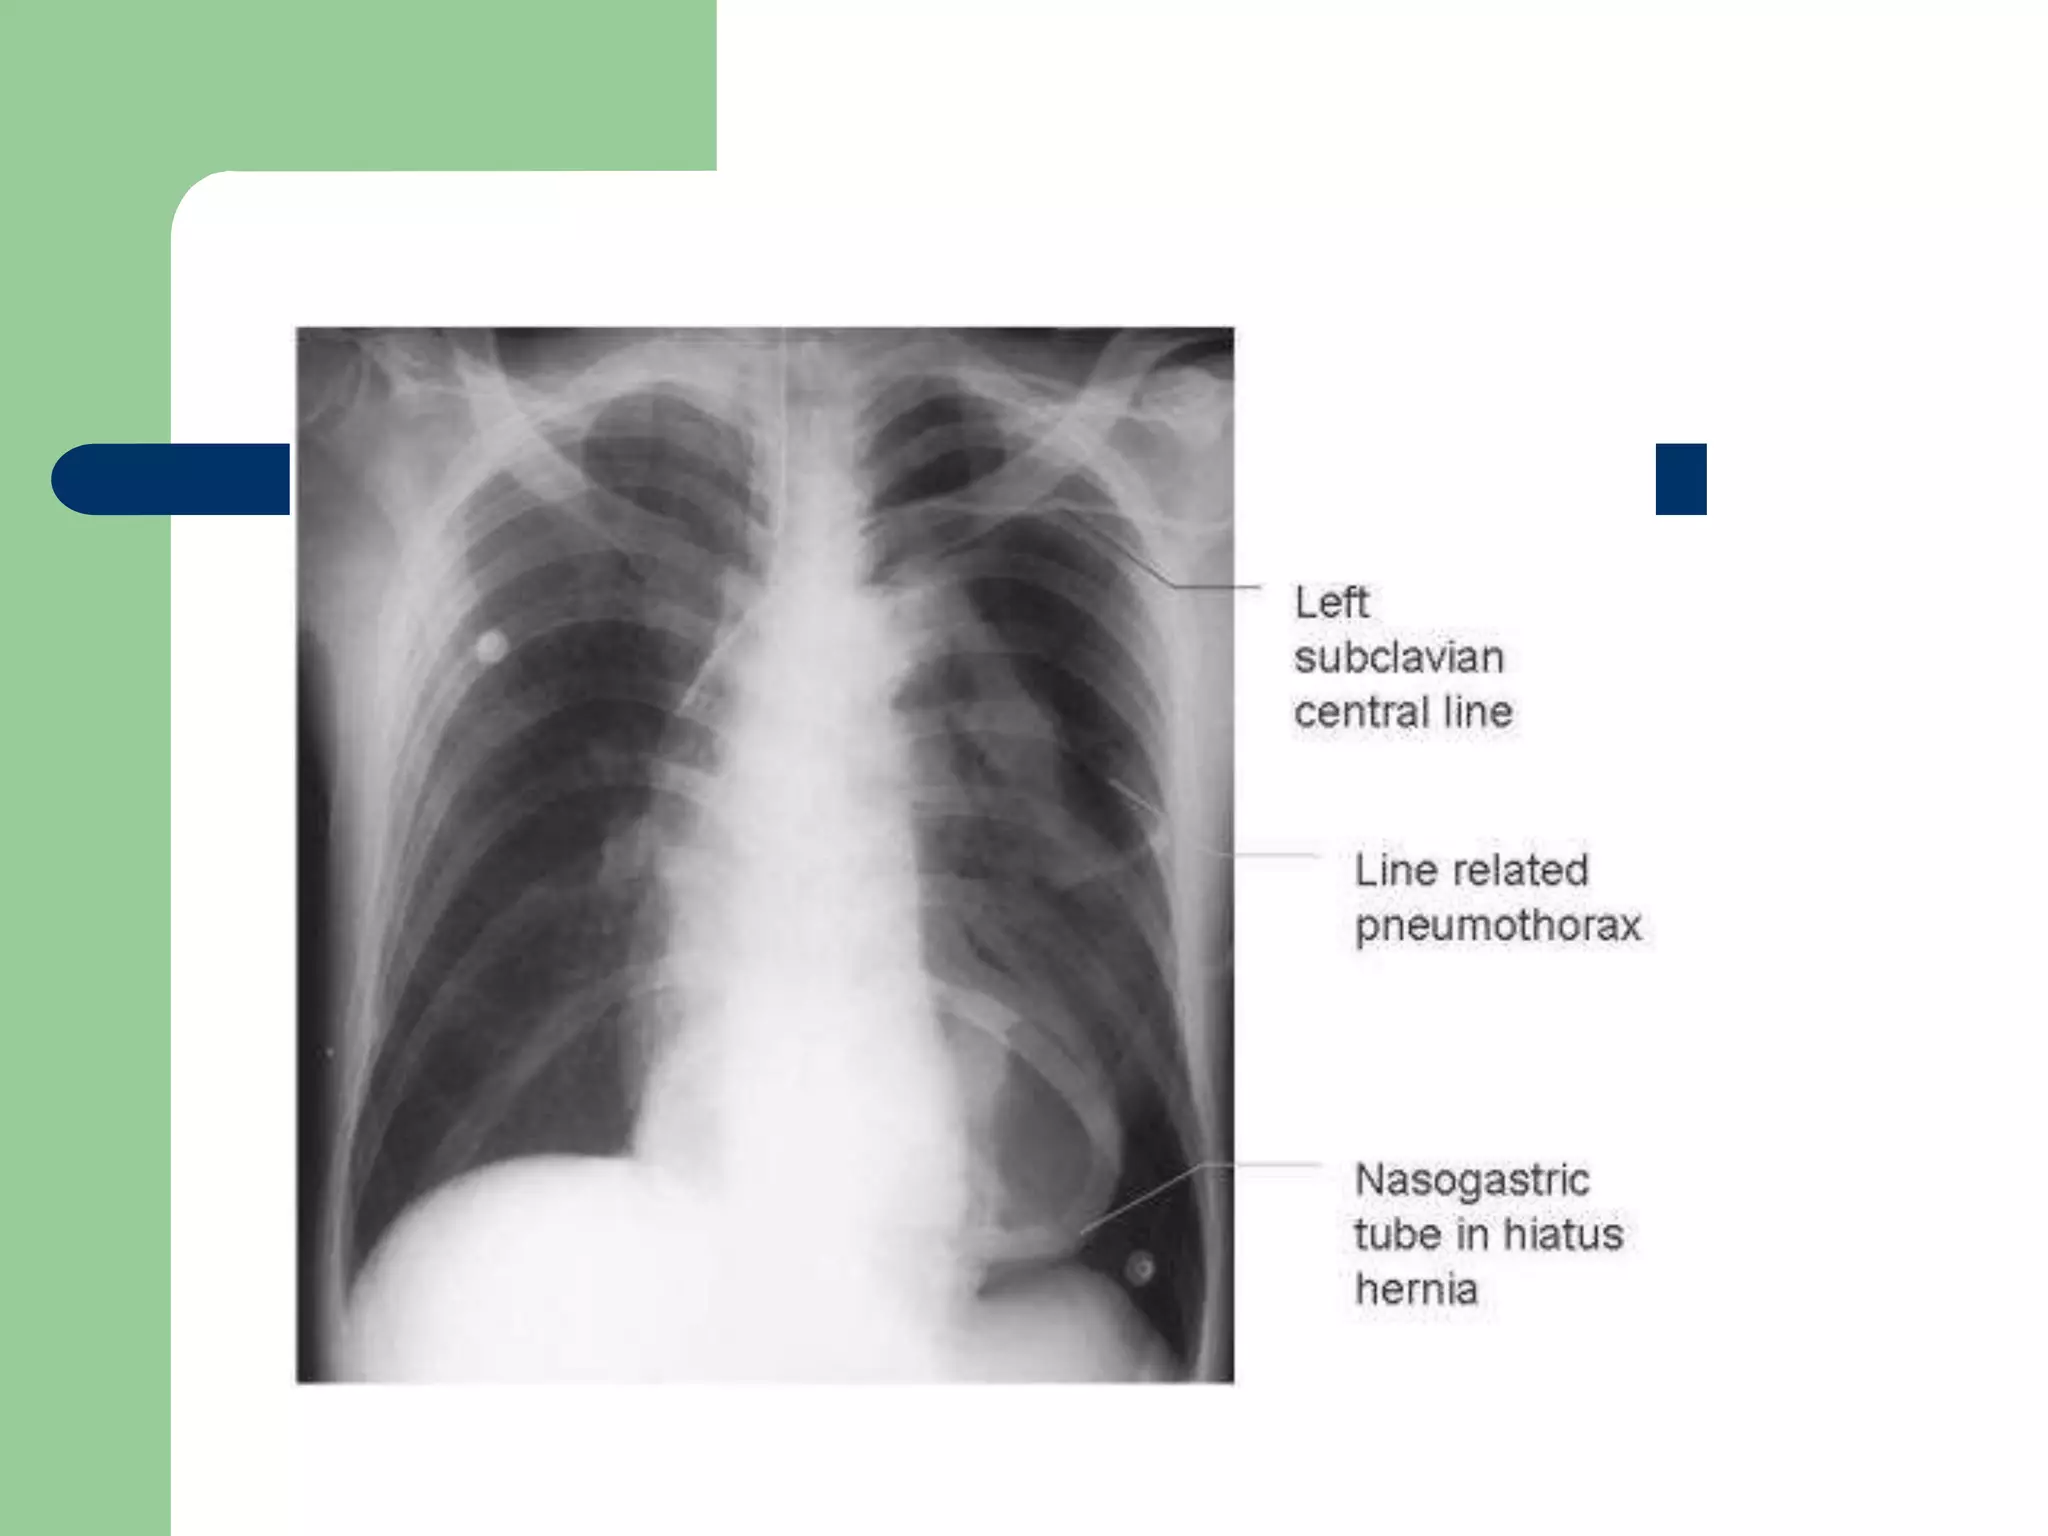

Correct IJ placement

CXR provided by Jeremy P. Feldman, MD

E-Bay Fellow in Pulmonary Vascular Disease

Correct IJ placement CXRprovided by Jeremy P. Feldman, MD E-Bay Fellow in Pulmonary Vascular Disease